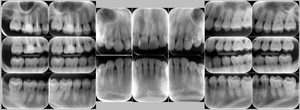

レントゲン写真

症例

基本情報

年齢・性別 41歳・男性

主訴 主訴:歯ぐきから出血する

治療部位:全顎

治療内容 1.歯周ポケット検査、資料取り(レントゲン写真14枚・口腔内写真)、歯磨き指導

2.歯磨き指導チェック、縁上の歯石除去

3.縁下の歯石除去4回

4.再評価(歯周ポケット検査・レントゲン写真14枚・口腔内写真)

5.メインテナンス

治療期間 1日

治療費 合計:14,160円

内訳(全て保険診療3割負担)

・初診検査、歯磨き指導、縁上の歯石除去:3,630円

・レントゲン写真、縁下の歯石除去①:3,040円

・縁下の歯石除去②:1,530円

・歯磨き指導チェック、縁下の歯石除去③:2,070円

・縁下の歯石除去④:1,530円

・再評価:2,360円

(2022年5月現在現在)

症例3

来院2回目、TBI後

SRP後

初診時、TBI前

年齢・性別 27歳・男性

主訴 主訴:左右下の歯ぐきに違和感がある

治療内容 1.歯周基本検査、レントゲン撮影、口腔内写真、歯磨き指導、歯石除去、着色除去

2.SRP(スケーリングルートプレーニング)、再評価

その他

3.親知らずの抜歯

4.カリエス処置:右上1.2.3左上1.2.3右下6左下7CR(レジン充填)、右下7セラミックIn

5.定期検診

治療期間 6ヶ月

治療費 ※歯周基本治療の費用:PMTC以外保険診療3割負担

合計:19,680円

1.初診検査(歯周ポケット検査.レントゲン撮影):3,010円

2.歯磨き指導、歯面の歯石除去:1,410円

3.PMTC(自由診療):5,500円

4.SRP(歯周ポケット内の歯石除去)×4回:約2,000円/回

5.再評価:1,760円

(2023年12月現在)

症例5

before

after

歯周病検査(治療前)

歯周病検査(治療後)

年齢・性別 32歳・男性

治療内容 「全顎」

歯周基本治療(歯周精密検査、スケーリング、OHI、SRP)

治療期間 約3ヶ月

治療費 歯周基本検査:約600円(保険診療3割負担)

スケーリング、OHI:約2,000円(保険診療3割負担)×2回

SRP、OHI:約1,500円(保険診療3割負担)×4回

歯周精密検査:約1,200円(保険診療3割負担)×2回

合計金額13,000円

(2025年2月現在)

担当者所見 初診時は、写真を見て分かるように、歯ぐきが赤く腫れていました。

また、歯周病の検査では、全体的に歯と歯の間の部分の歯周ポケットが4ミリあり、全体の約81%から出血が認められました。

出血量も多く、歯ぐきに触れた瞬間に出血しました。

レントゲンで骨のレベルがしっかりとあることが確認できました。

そのため、ご自身で正しい歯磨きを継続することで改善すると考えました。

歯周基本治療を経て、再度検査した結果、歯周ポケットはほぼ3ミリ以下に改善しました。左下7番の残存した歯周ポケットは、隣の親知らずを抜いたため経過観察します。

出血率は約4%まで改善し、出血量も点状で少なくなりました。

今後は右上2番、右下3番の歯ぐきの発赤の改善と、出血率0%を目指して、定期検診でメンテナンスしていきます。